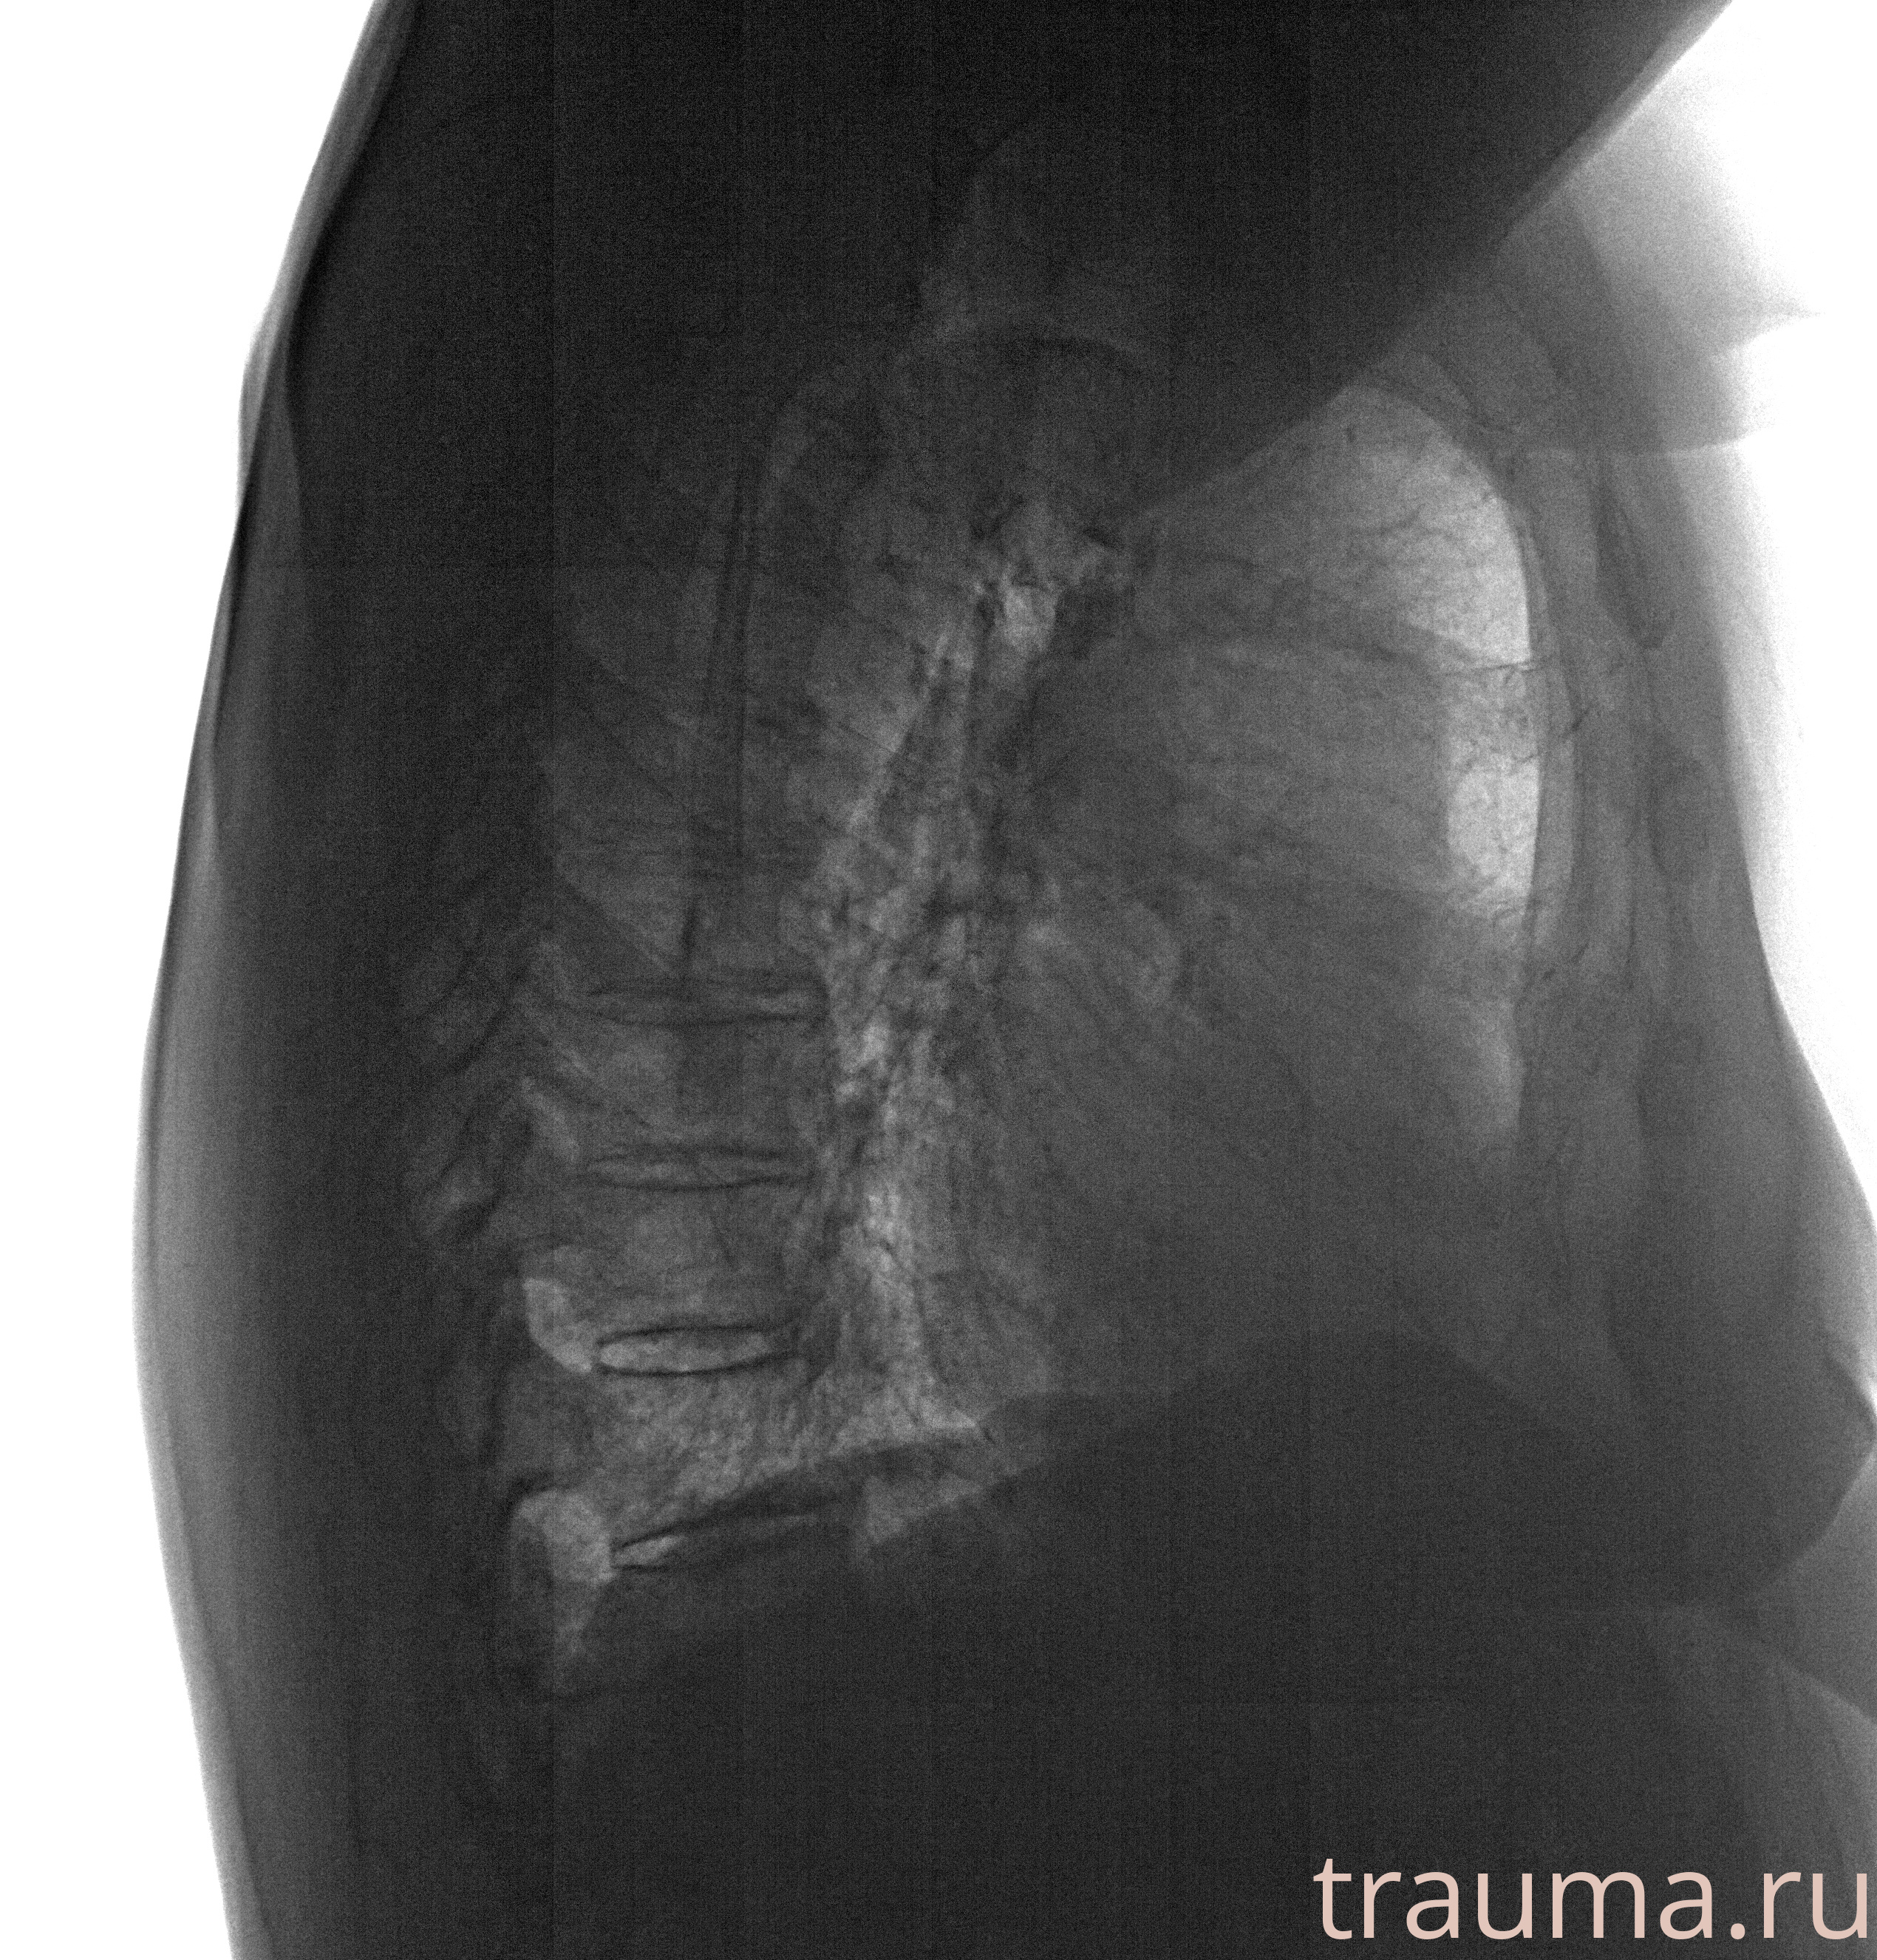

Рентгенограммы

Рентген на дому: по вашему адресу приезжает врач-рентгенолог, травматолог-ортопед с мобильным рентгеновским аппаратом, проводит диагностику травмы или заболевания, делает необходимые рентгенограммы, дает рекомендации по дальнейшему лечению. Получить качественные снимки в домашних условиях возможно благодаря уникальной методике, разработанной МосРентген Центром для института  Склифосовского

при переломе шейки бедра и пневмонии от компании МосРентген Центр - партнера Института имени Склифосовского